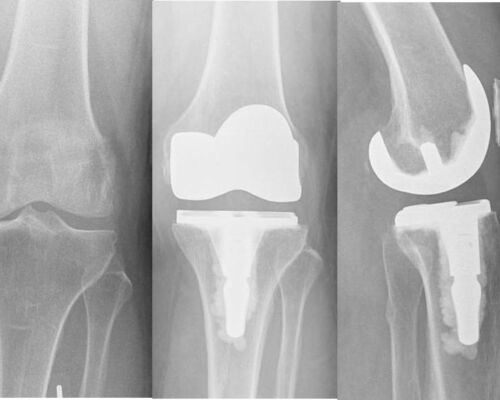

JOINT REPLACEMENT / ARTHOPLASTY

Advanced knee arthritis – left image,

Total knee replacement – right image